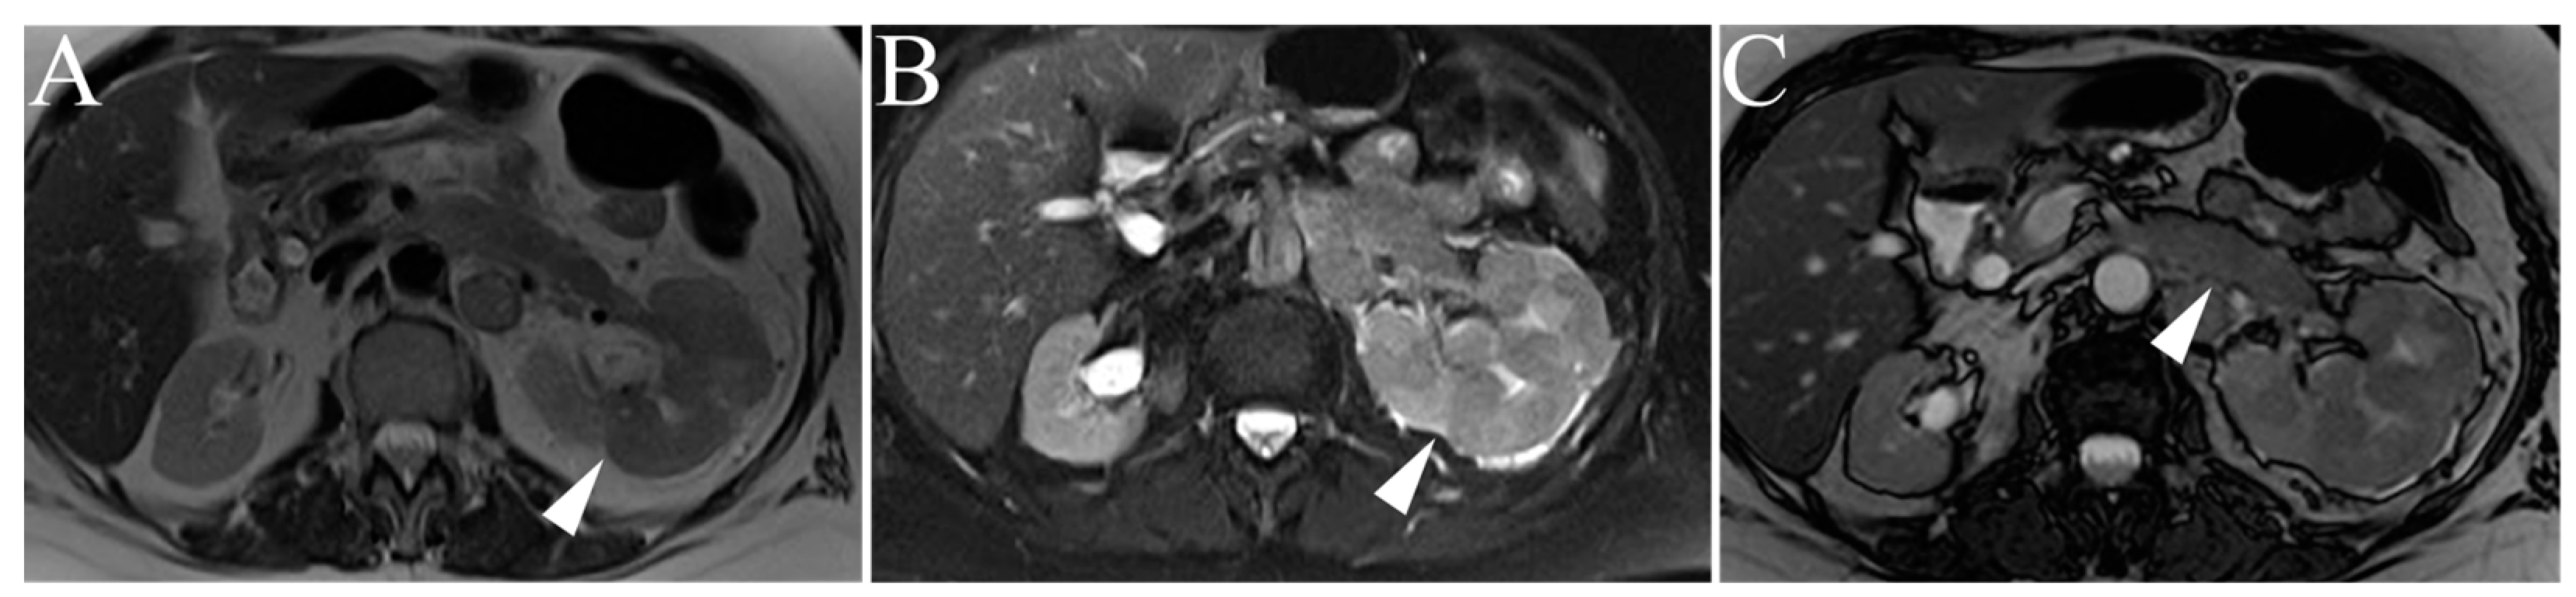

| Angiomyolipoma | High T2-intensity signal due to fat content. Low T2 on fat-suppressed images. Microscopic, intracytoplasmic fat made apparent with in- and out-of-phase GRE |

| Lipid-poor Angiomyolipoma | T2-hypointense Macroscopic fat and/or absence of fat High arterial enhancement with subsequent washout |

| Oncocytoma | T2-iso-to-hyperintense relative to normal parenchyma Central/eccentric T2-hyperintense scar Delayed enhancement of a central scar Segmental enhancement inversion pattern |

| Clear Cell RCC | Heterogenous, high T2-intensity Avid enhancement in corticomedullary and nephrogenic phases Microscopic fat as see on dual echo T1W in- and out-of-phase Invasion into surrounding vessels (esp. renal vein or IVC) Presence of necrosis or intralesional calcification |

| Type 1 Papillary RCC | T2-hypointense Uniform progressive delayed enhancement Well-circumscribed, homogenous, peripherally-located |

| Type 2 Papillary RCC | Heterogenous T2 signal intensity Heterogenous enhancement Larger with more indistinct margin vs versus Type 1 pRCC |

| Chromophobe RCC | Low to intermediate T2-intensity Intermediate, delayed enhancement Central, stellate scar with “spoke-wheel” enhancement pattern Peripheral, homogenous, well-circumscribed Mimics oncocytoma on imaging |